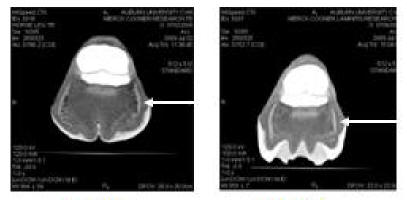

[Fig 6 above] Computed tomography image of foot 1 and foot 3,

note the differences in the shape of the heel, and the differences

in the collateral cartilages (arrow)